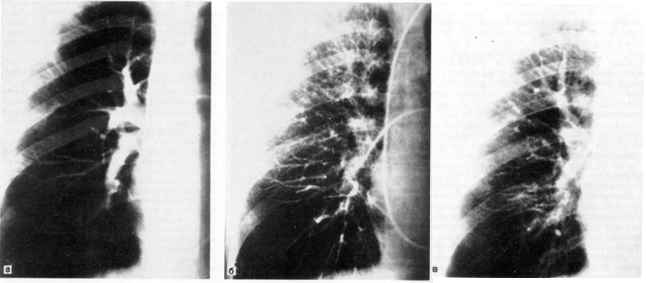

Бронхография легких может быть выполнена под наркозом. Особенность ее проведения заключается в том, что больной лежит на спине, осуществляется искусственная вентиляция легких в условиях миорелаксации. Контрастное вещество вводят через интубационную трубку и в период кратковременного апноэ выполняют рентгенограммы обоих легких в прямой и косых проекциях (рис. 5).

Рис. 5. Поднаркозная бронхография у ребенка. Косая проекция. Норма.